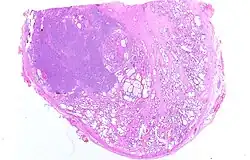

Mikroskopische Pathologie

97 % aller Prostatatumoren sind Adenokarzinome, das heißt, sie entstehen aus entarteten Drüsenzellen. Ein Übergangsstadium zum manifesten Krebs wird als prostatische intraepitheliale Neoplasie (PIN) bezeichnet und entspricht einem Carcinoma in situ. Beim eigentlichen Karzinom kommen verschiedene histopathologische Wachstumsmuster vor, auch gleichzeitig nebeneinander: glandulär beziehungsweise azinär (drüsenartig), kribriform (siebartig) und solide. Das Ausmaß der Entdifferenzierung ist Grundlage des Gradings. 40–50 % der Tumoren liegen bei Diagnosestellung multifokal vor.[54]

-

Normales Prostatagewebe -

Prostatische intraepitheliale Neoplasie (PIN) -

Karzinom vom azinären Typ -

Entdifferenziertes Karzinom

Knochen- und Weichteilmetastase eines Prostatakarzinoms mit immunhistochemischem Nachweis einer PSA-Expression (braun)

Die Nicht-Adenokarzinome (weniger als drei Prozent) sind meist urothelialer Herkunft, leiten sich also aus dem Übergangsgewebe der Harnröhre oder -blase ab (siehe Blasenkrebs). Äußerst selten sind Sarkome (Leiomyosarkom, Fibrosarkom, Rhabdomyosarkom) des Stromas beim Erwachsenen. Bei Kindern sind Rhabdomyosarkome die häufigste Form des Prostatakrebses, werden aber nicht wie bei erwachsenen Patienten als Prostatakarzinom aufgefasst, sondern als Weichteilsarkom.[68][69]